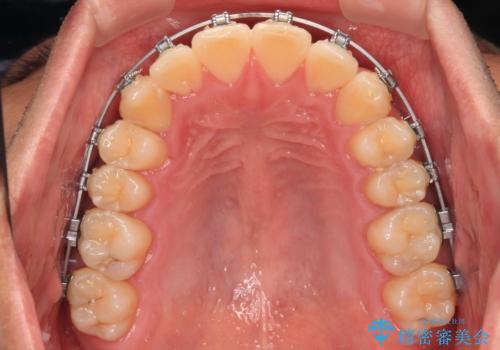

- 矯正装置

- メタルブラケット

1年強でワイヤー装置を外すことができ、思ったよりも短期間で終了したため、患者様には大変喜んでいただきました。